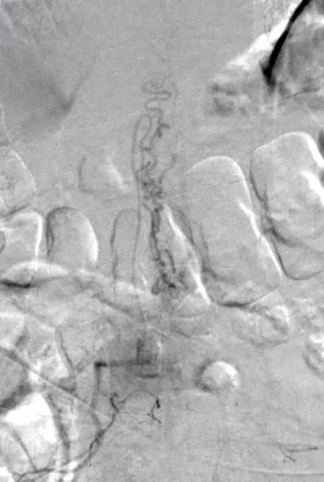

完善术前检查、排除禁忌症,并向患者及家属充分沟通手术必要性及风险后,手术顺利开展。术中,郭晓宾主任凭借丰富经验,在局部麻醉下经股动脉穿刺插管,将导管逐一超选脊髓供血动脉,于DSA设备引导下注入造影剂,清晰显示病变为双侧腰二动脉供血动静脉畸形合并动静脉瘘,为后续治疗提供了重要依据。手术全程顺利,患者生命体征平稳,无并发症。